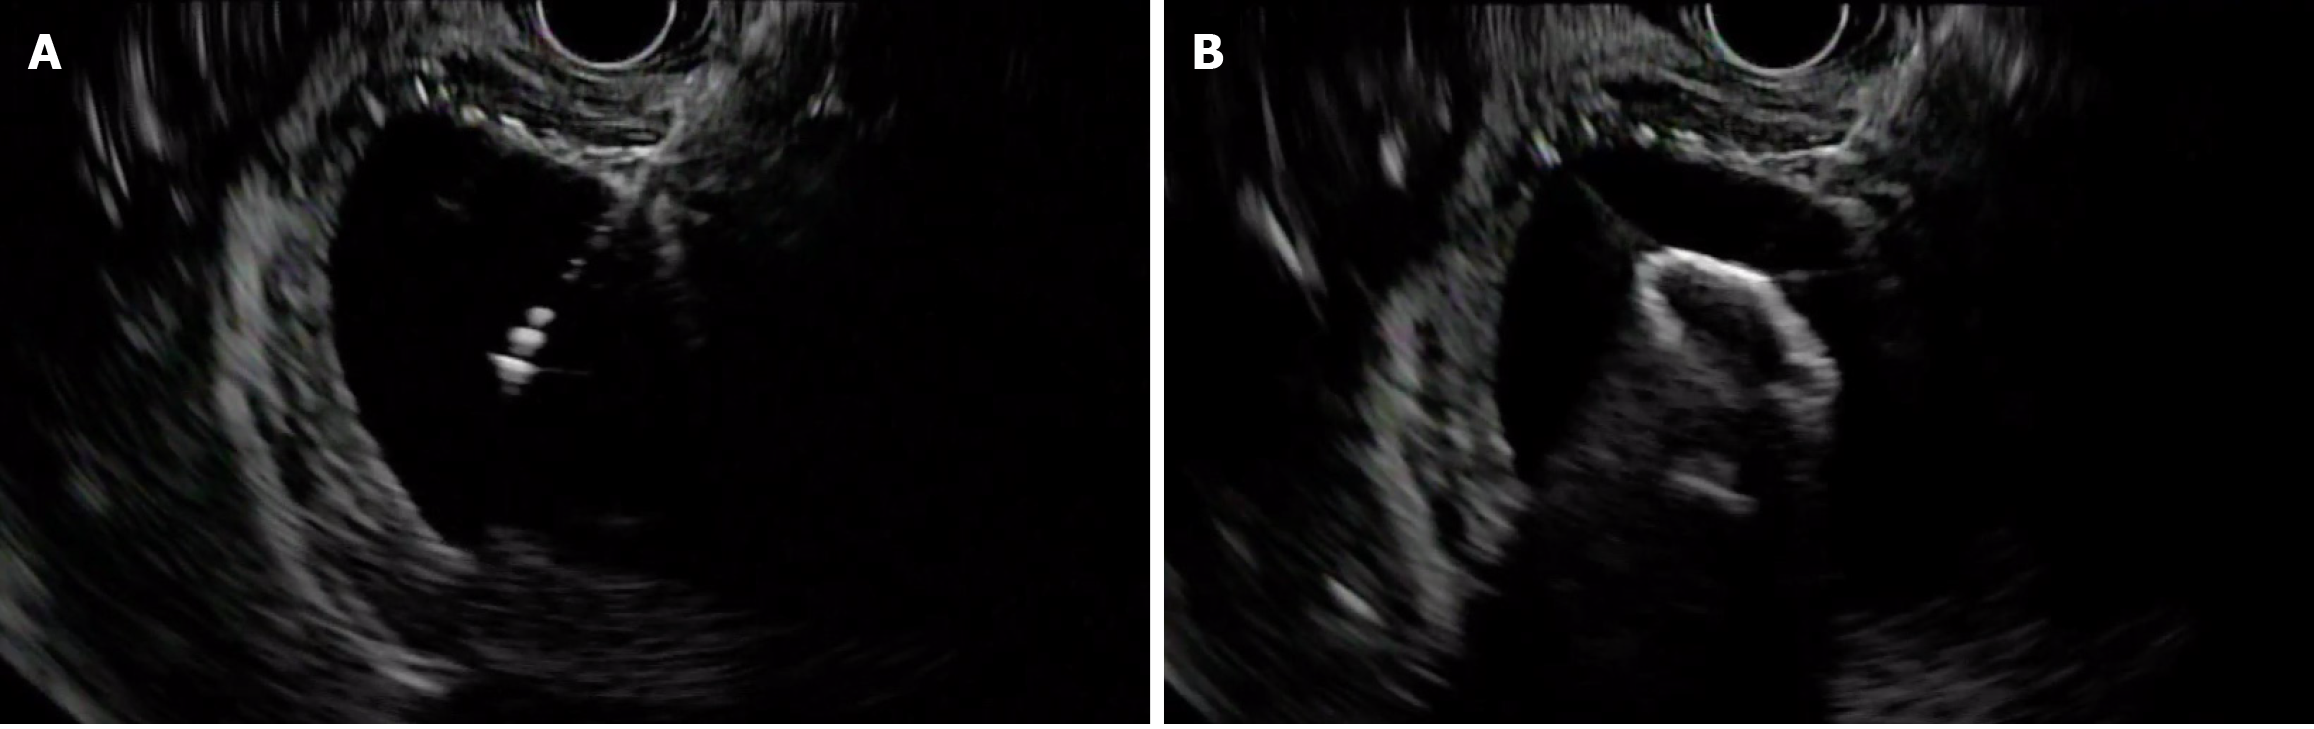

Figure 1

Endoscopic ultrasound transduodenal view of dilated gall bladder lumen with thickened wall.